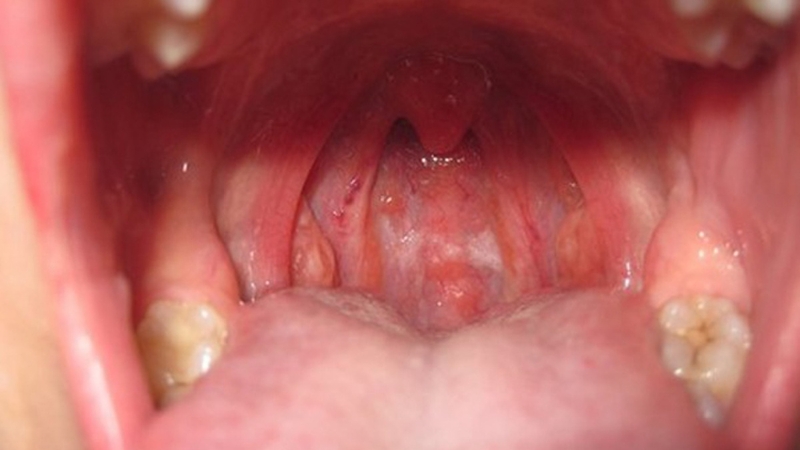

Viêm họng hạt xảy ra khi vùng hầu họng bị viêm nhiễm kéo dài, các mô lympho ở thành sau họng phải làm việc trong thời gian dài, từ đó dẫn đến chúng bị phình to ra thành các hạt. Các hạt này có kích thước không đồng nhất, có hạt bằng đầu kim có hạt bằng hạt đậu. Viêm họng hạt là một dạng viêm họng mãn tính quá phát.

Mách bạn một số cách trị viêm họng hạt tại nhà 1

Viêm họng hạt có thể xảy ra ở mọi đối tượng mọi độ tuổi